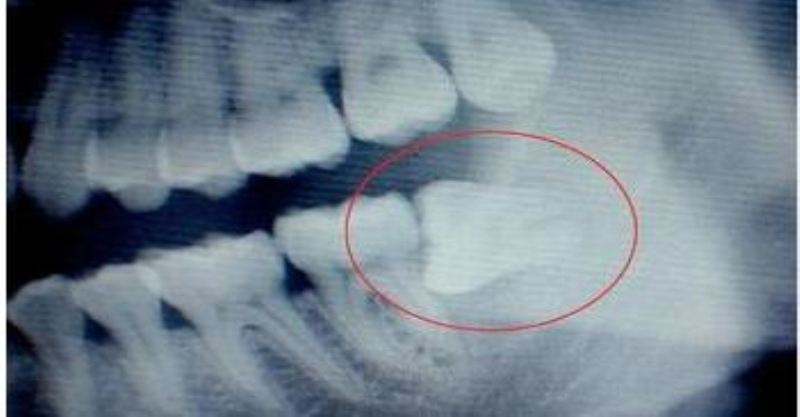

3、横向阻生的智齿

横向阻生的智齿容易将邻牙挤压后,造成邻牙受损,甚至还易导致牙齿变得拥挤不齐,清洁难度加大,提高齿病的发生几率。